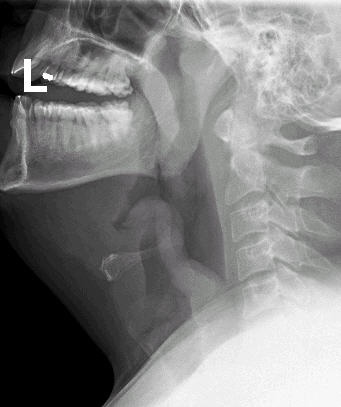

Lateral neck film demonstrating epiglottitis

From Dr Petri's personal collection; used with permission